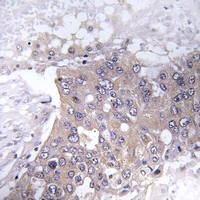

IHC (Immunohiostchemistry)

(Immunohistochemical analysis of JAK2 (pY221) staining in human liver cancer formalin fixed paraffin embedded tissue section. The section was pre-treated using heat mediated antigen retrieval with sodium citrate buffer (pH 6.0). The section was then incubated with the antibody at room temperature and detected using an HRP conjugated compact polymer system. DAB was used as the chromogen. The section was then counterstained with haematoxylin and mounted with DPX.)